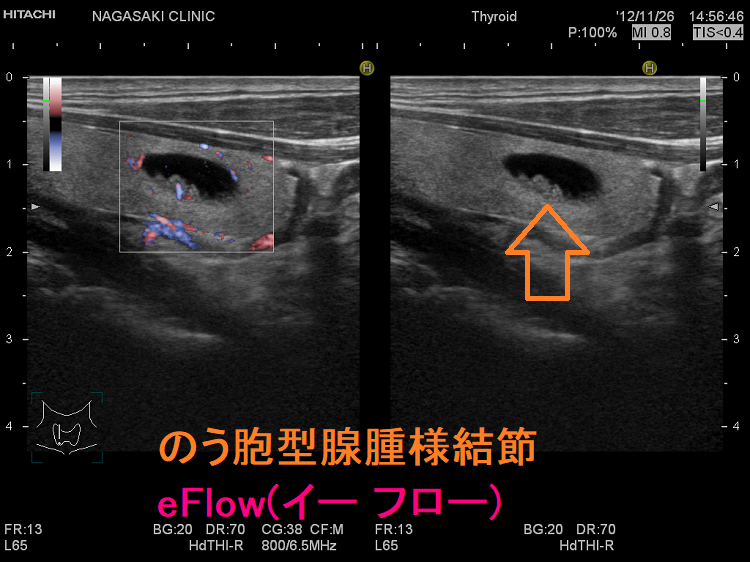

甲状腺のう胞に見えるが実は甲状腺腫瘍

甲状腺のう胞(甲状腺嚢胞)に見えるが甲状腺腫瘍 超音波(エコー)画像;低エコー(真っ黒)で、内部にコロイド様物質があるように見えるため、甲状腺のう胞(甲状腺嚢胞)と間違えます。

甲状腺のう胞に見えるが実は甲状腺腫瘍 eFlow

甲状腺のう胞(甲状腺嚢胞)でなく甲状腺腫瘍  eFlow(イー フロー);内部血流が、はっきり見えて甲状腺腫瘍なのがわかります。